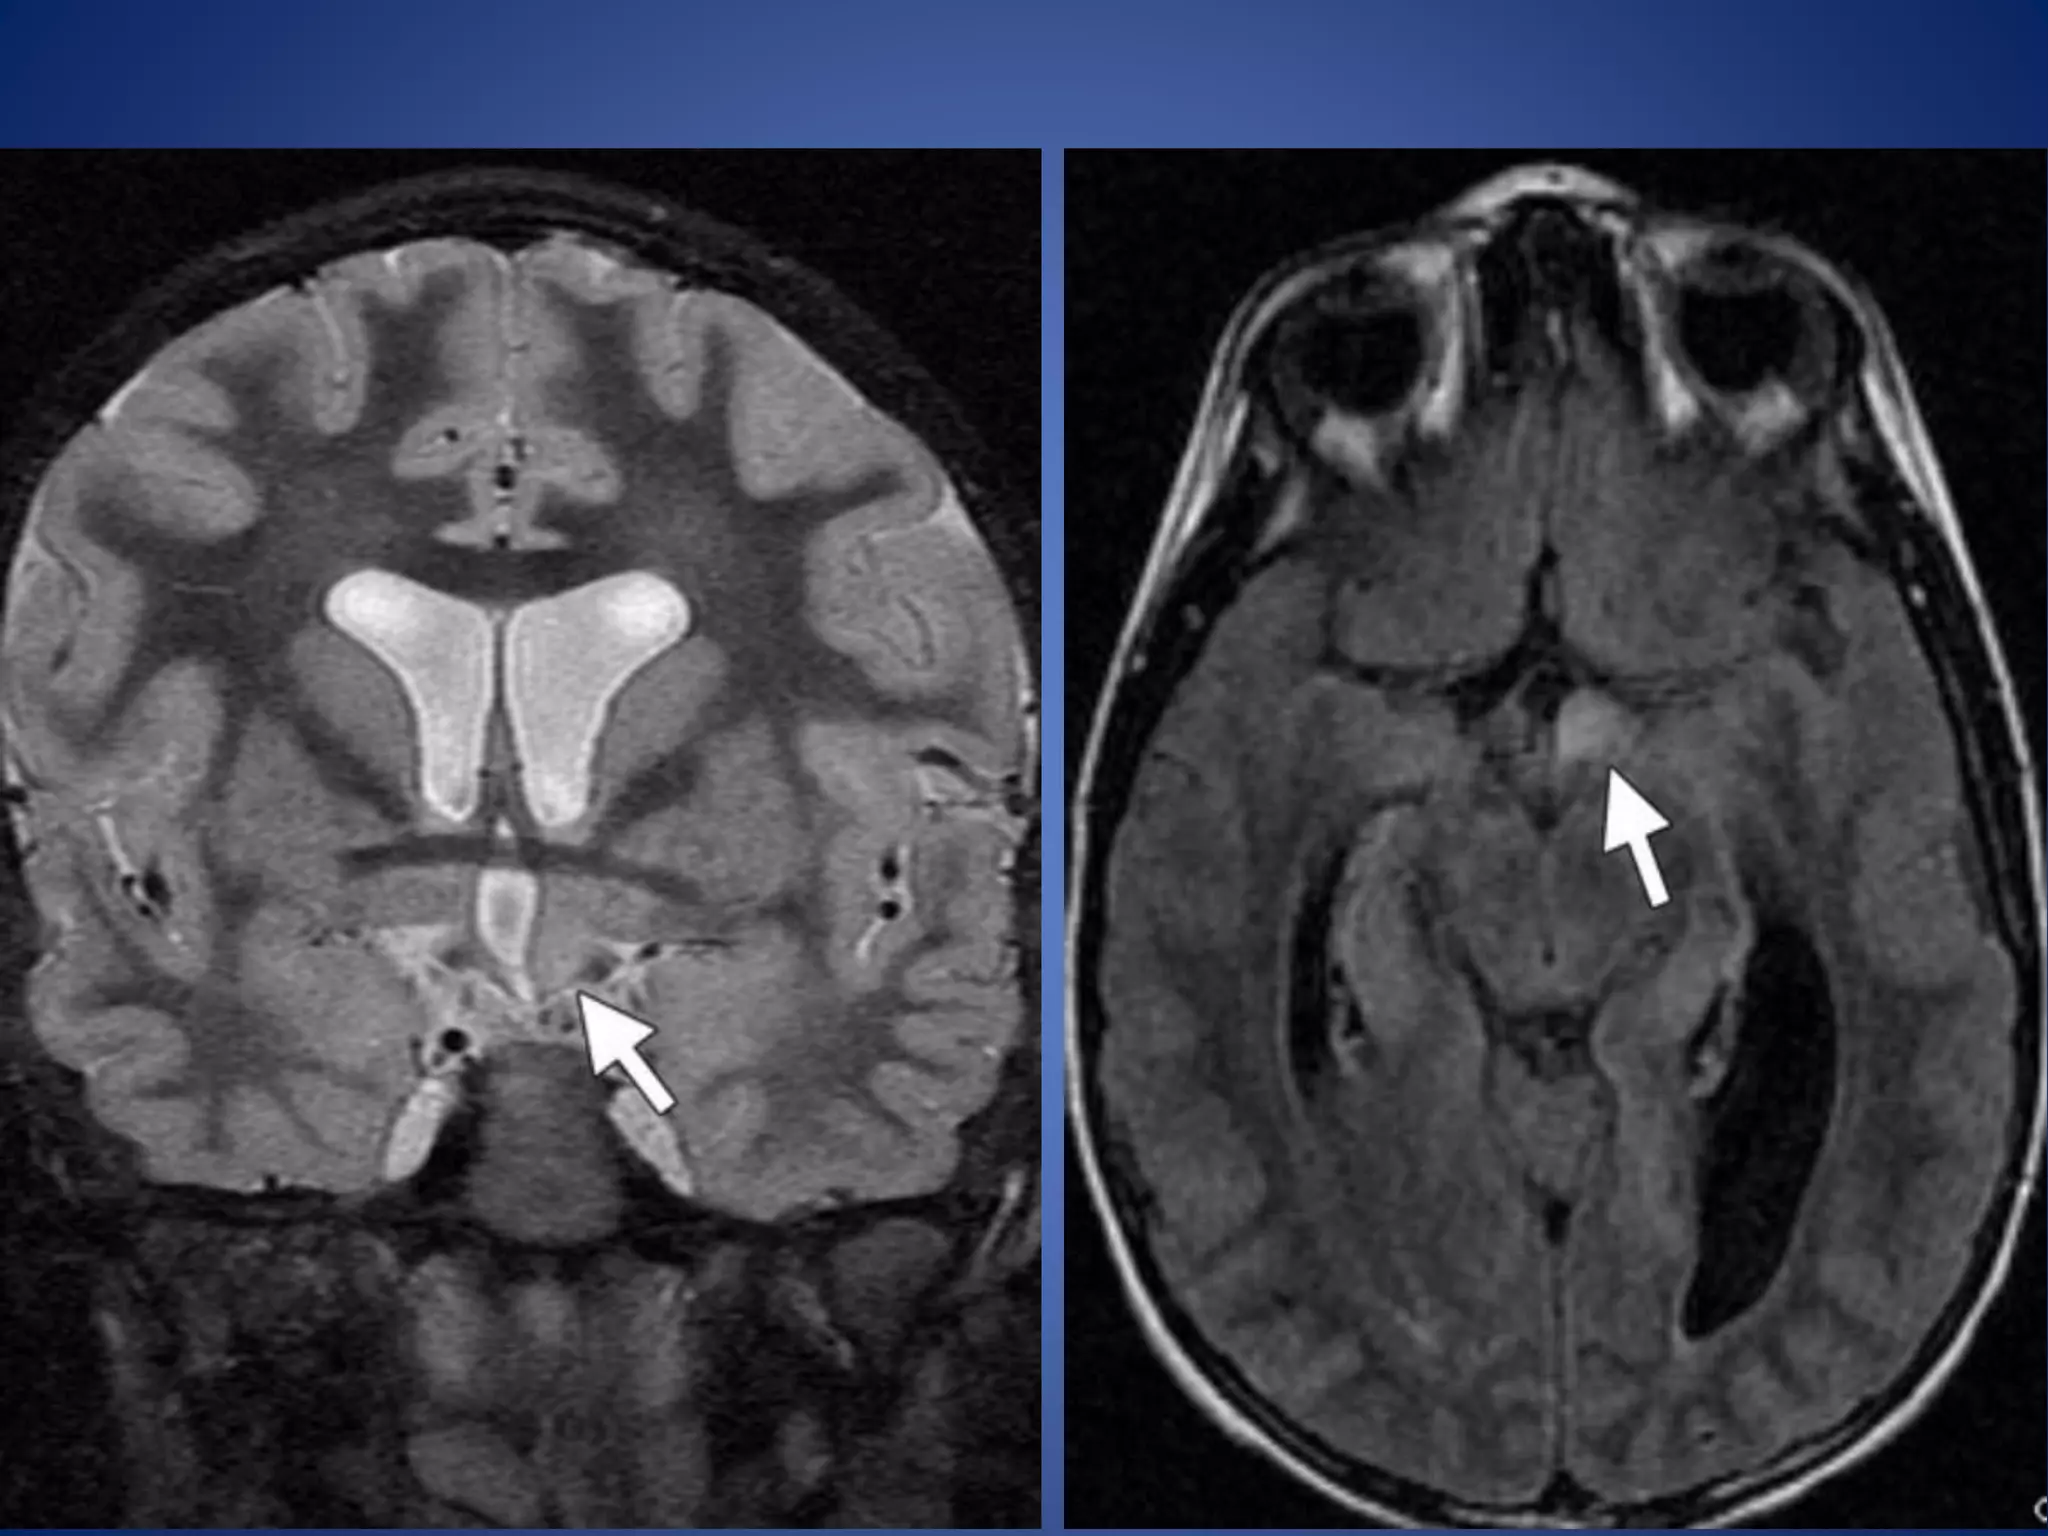

• #20 Suprasellar germinoma in an 8-year-old girl. (a) Coronal T2WI reveals a heterogeneous mass with hyperintense cystic spaces in the suprasellar region (arrow)

• #21 (b) Axial T1-weighted image reveals an isointense mass with hypointense cystic areas (arrow) splaying the cerebral peduncles

• #22 enhancement of the solid components of the mass (arrow)